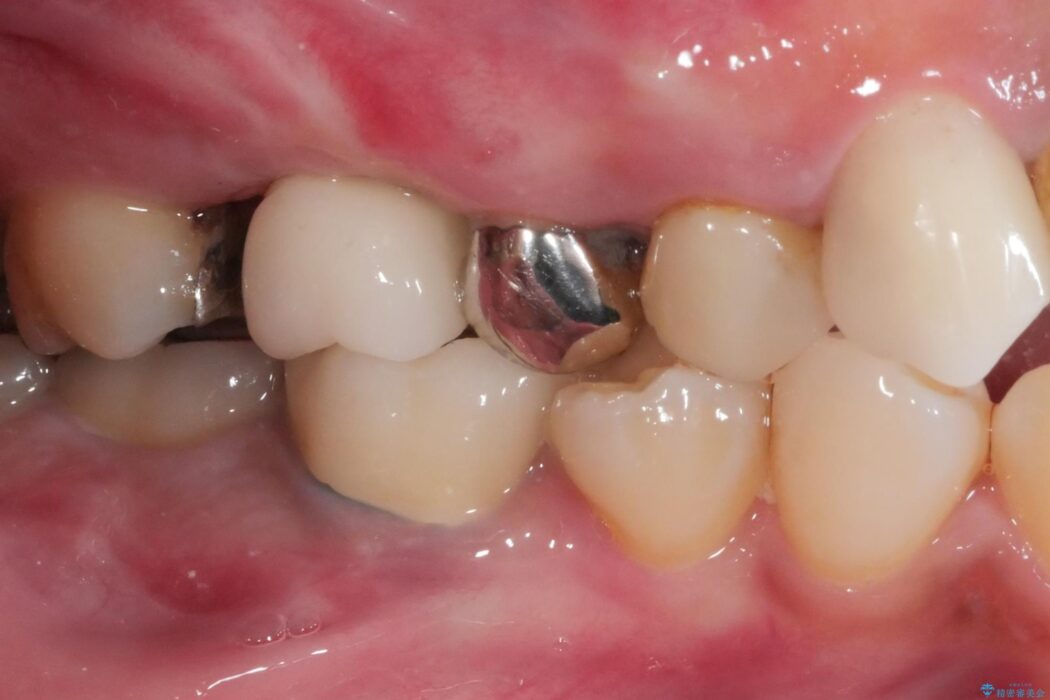

治療後について

インプラント治療により、問題なく奥歯で噛めるようになり喜んでいただけました。

しかし、奥歯の嚙み合わせが強いため、インプラント周囲の骨吸収や他の歯の破折等が起きる可能性があります。

就寝時のマウスピース装着と定期的なメンテナンスが重要となります。